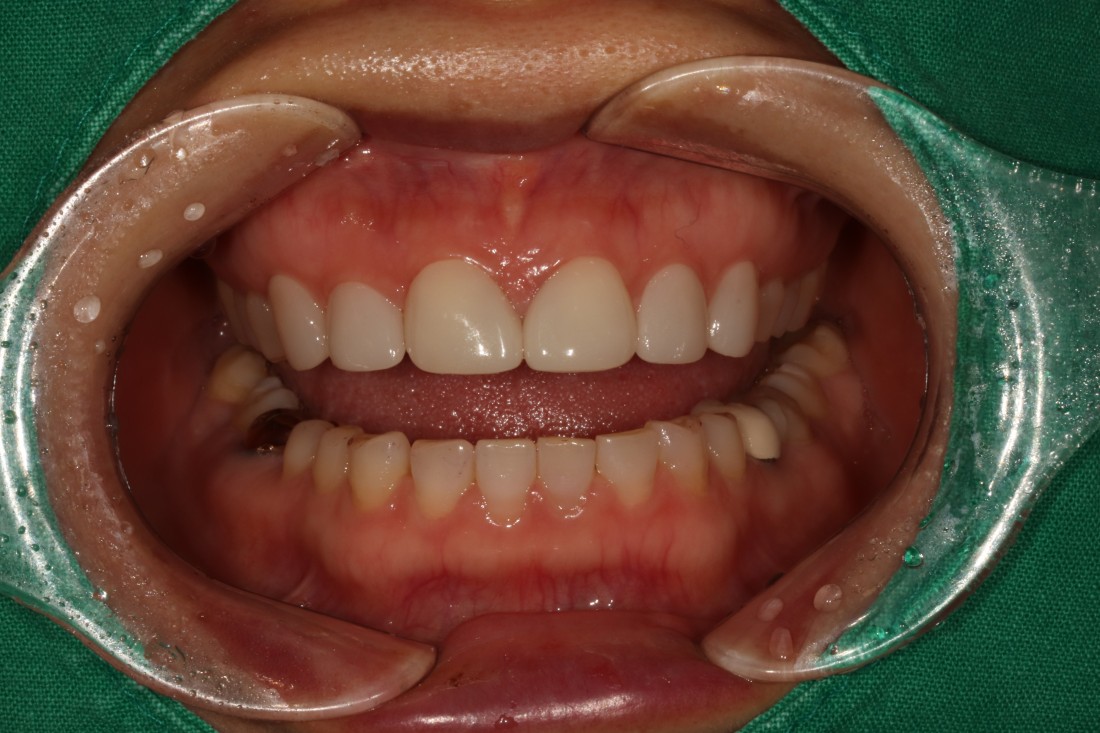

광주 라미네이트 치과 중에서

라미네이트 관련 강의를 하시면서

서울 강남 의료진이 직접 진료하는

라미네이트치과는 오직

서울우리아이치과의 새로네이트 뿐입니다.

서울 강남까지 가지 않으셔도

서울 의료진의 기술과 실력 그대로

광주광역시 라미네이트 치과에서

받아보실 수 있습니다.